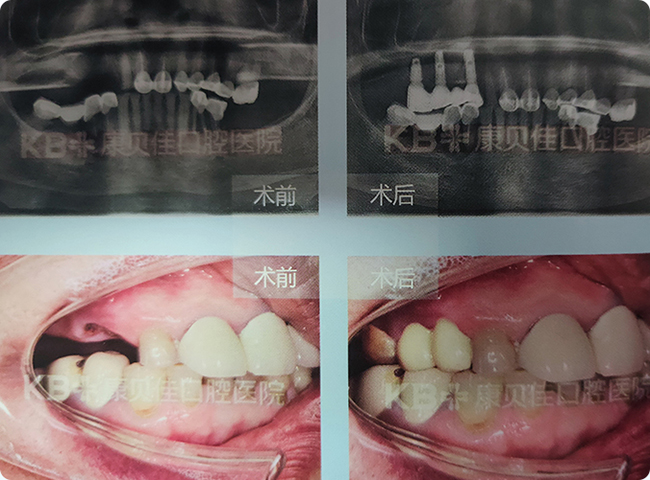

曹女士 74岁

牙本质本身就不好,得了干燥综合症后整口牙不是蛀牙就是缺损,影响进食。曾到多家口腔医疗机构要求修复缺牙,均遭到拒绝。康贝佳国际种植牙专家团经过评估后为其定制了微创即刻种植修复方案,成功帮其恢复了一口好牙。患者心里充满感激,送来锦旗表达谢意。

治疗方案:

上颌种植4颗恢复5颗 下颌种植7颗恢复13颗